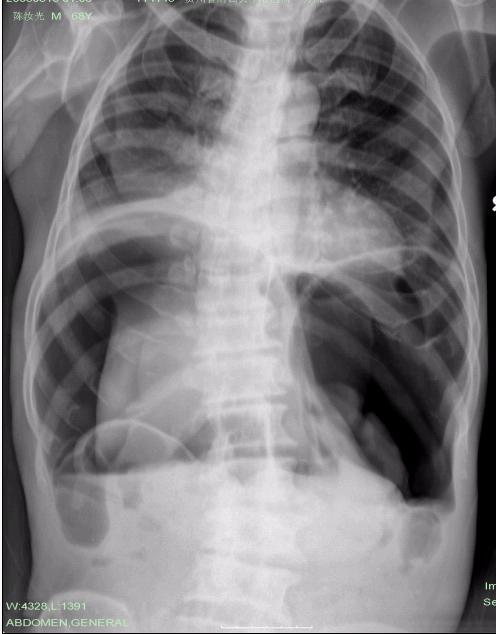

男,68岁,腹痛20多天。

补充:第一张(胸片)的左右搞错了。真对不起!

气腹成这样能忍受,不是痛阙高就是反射弧有问题,([悄悄话]要不就是cp?)

气腹,好病例。

气腹?..........我还以为肠梗阻呢?张力那么高!!!不要搞错了浪费病人的病情就行~~~~~

气腹,多以胃肠道穿孔多见。

气腹,见宽大气液平, 太恐怖啦吧。

典型的大量气腹----消化道穿孔。

大量气腹。考虑胃肠穿孔可能。

大量气腹;多为腹部空腔脏器穿孔所致。